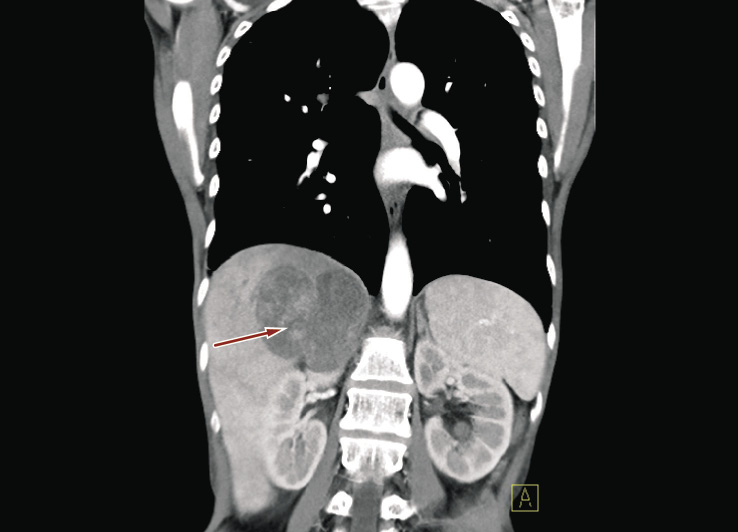

Physical examination revealed a tender palpable right upper quadrant mass. Laboratory studies were significant for anemia (6.2 g/dl) and leukocytosis (1.19 × 103/µl). Hormone panel including serum and urinary metanephrines, serum and urinary cortisol, plasma aldosterone, and serum adrenocorticotropic hormone was normal. Ten days after hospitalization, follow up chest-abdomen and pelvis CT scan revealed enlargement of the adrenal mass from 45 × 29 mm to 65 × 45 mm. New bilateral lung nodules were also noted (Figures 3 and 4).

Figure 3. CT scan revealing growing adrenal mass (red arrow) with extensive infiltration of liver and upper pole of kidney (longitudinal plan, ten days after hospital admission)